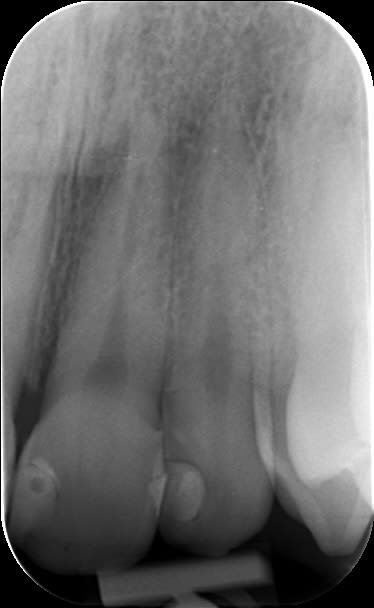

Retour d'expérience avec du Gaenial après quelques cas. Ca tient bien la route, cependant il faut oublier le pinceau silicone qui étale mal ce produit. C'est moins évident de caractériser les bords libres, on obtient une sorte de flou de translucidité entre le transparent TE (opalescent?) et les teintes émail (le plus souvent JE), ce n'est pas aussi net et délimité que chez Micérium, mais l'effet caméléon est cependant plus présent avec le GC ce qui permet d'obtenir un bon résultat plus rapidement. Pour le cas présenté ça donne environ 1H30 pour 2 composites "spot" sur 13 (mésial) et 12 (disto-palatin), 1 composite de bonne taille sur 12 (mésio-vestibulaire), et 2 facettes composite directes sur 11 (vitale), et 22 (dévitalisée), y compris pose/dépose digue, retouche bord libre de la CCM (antédiluvienne), mise en forme et polissage à 90%

L'idée ici est d'améliorer un sourire et de motiver la patiente à un traitement ultérieur de bonne qualité, elle n'a pas de moyen pour l'instant de reprendre la 21, qui présente une face vestibulaire plate, un manque de soutient de la gencive, et une adaptation radiculaire médiocre, cependant c'est cette 21 qui devient pour l'instant l'élément de référence pour le montage composite, et avec cette vision là, la forme de 11 et 12 est en harmonie (voir même presque trop volumineuse) avec la 21.

Plus tard, dès que ses moyens ( ou sa prise de conscience sur l'état de ses dents et des moyens qui existent pour améliorer la situation) vont le permettre, une proposition esthétique plus global, lui sera proposée et a ce moment là les volumes seront définis par des Mock-up.

On peut "bricoler" avec des composites, cela reste souvent moins délabrant que de la prothèse céramique, mais l'esthétique final et le pronostic sont très souvent moins bon. Je suis persuadé que cette patiente nécessite une prise en charge globale.